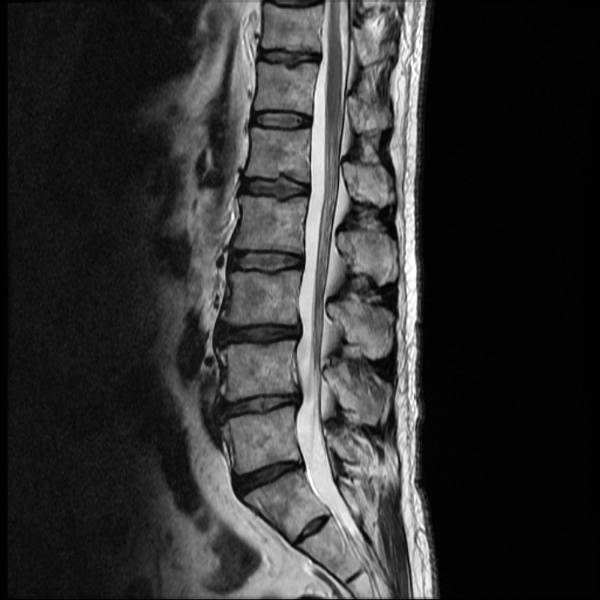

Andere Untersuchungen, die zur Diagnose eines Bandscheibenvorfalls durchgeführt werden können, sind Magnetresonanztomographie (MRT), Computertomographie (CT), Myelographie und Elektromyographie (3). Welche Methode am besten geeignet ist, hängt vom Patienten und seinem allgemeinen Gesundheitszustand ab.

Ein MRT verwendet ein starkes Magnetfeld und Radiowellen, um detaillierte Bilder der inneren Strukturen des Körpers, in diesem Fall der Weichteile im Hals, zu erstellen. Die Untersuchung kann einen Bandscheibenvorfall identifizieren, indem sie die Größe und die Lage des Vorfalls zeigt. Ärzte verwenden diese Art der bildgebenden Untersuchung, weil sie ihnen auch hilft, andere Ursachen für Nackenschmerzen, wie z. B. Tumore, auszuschließen.